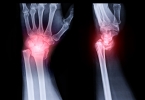

产后手关节疼痛时,用热水泡手通常能有所帮助,但效果取决于疼痛的具体原因。如果疼痛是由于受凉或缺钙等因素引起的,热水泡手可以有效缓解症状。然而,如果疼痛是由某些疾病因素导致的,可能就不适合使用热水泡来处 ...